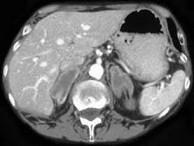

问题 男,65岁,体检时超声发现双侧肾上腺肿块,CT检查如图所示,请结合图像,选择最佳答案 ( )

选项 A、双侧肾上腺增生 B、双侧肾上腺腺瘤 C、双侧肾上腺结核 D、双侧嗜铬细胞瘤 E、双侧肾上腺转移瘤

答案 E